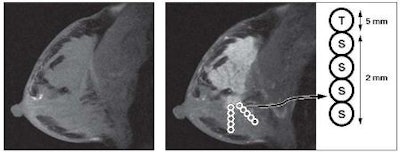

Hattangadi and her team performed signal enhancement ratio analysis of nontumor breast tissue on dynamic contrast-enhanced MR scans of 42 women. All of the patients had invasive breast cancer that had been confirmed by core biopsy or fine-needle aspiration before treatment; each woman received neoadjuvant chemotherapy for invasive breast cancer (scan one) and after one cycle of chemotherapy (scan two) between 1995 and 2002.

For each MR scan, signal enhancement ratio values from each region of interest (ROI) in breast tissue were characterized relative to their position, the distance from the edge of visible tumor. The mean number of ROIs for each patient was 8.5. When the team compared tumor signal enhancement ratio values with stromal signal enhancement ratio values, the mean signal enhancement ratio values from ROIs in visible tumor were higher than those in stroma.